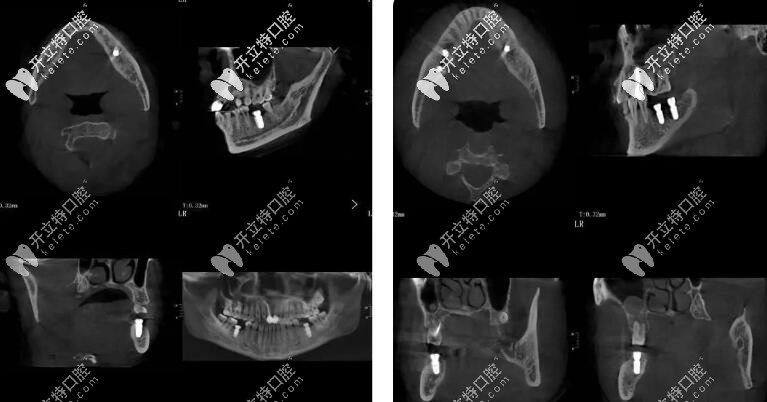

50歲的李先生,長(zhǎng)期有不良的口腔習(xí)慣,導(dǎo)致全口牙齒大部分缺失, 現(xiàn)在的情況就是進(jìn)食困難、無(wú)法完成咀嚼,再后來(lái)顳下頜關(guān)節(jié)紊亂,去了不少醫(yī)院但是解決不了問(wèn)題。

后來(lái)從朋友處打聽(tīng)到朱院長(zhǎng),朱院長(zhǎng)從抬高咬合到頜重建到塊狀骨移植,再?gòu)能浗M織增量到美學(xué)塑形,解決了李先生的難題。

簡(jiǎn)單的來(lái)說(shuō)就是從吃飯咬不動(dòng)、嚼不碎再到咬合正常,并且恢復(fù)了全口的咀嚼功能。

種植牙手術(shù)